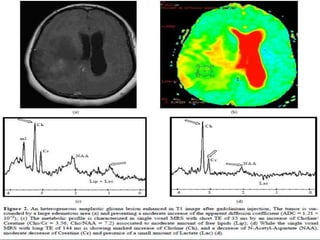

Forty-nine-year-old woman with a glioblastoma in the frontal lobes. The

region within the tumour with pronounced signal enhancement is marked

with circle on ASL CBF, DSC rCBF (colour-coded) and DSC rCBV (grey scale).

A 22-year-old man with centrally located

glioblastoma multiforme (WHO IV).

A, Tumor shows heterogeneous hyperintensity

with prominent peritumoral edema and/or

tumoral infiltration (arrow) on axial T2-

weighted SE image (2295/90). B, There is a

significant heterogeneous enhancement in

tumoral borders but not in peritumoral area

(arrow) on axial T1-weighted image (583/15).

C, Gradient-echo axial perfusion MR image

(627/30) with rCBV color overlay map shows

both high rCBVT value of 6.58 and rCBVP value of

2.21, which are consistent with HGGT.

Peritumoral increased rCBV (arrow) shows

tumoral infiltration outside the tumoral

margins, which is not perceptible on T2- and

contrast-enhanced T1-weighted images.

D, Time-signal intensity and gamma-variate

fitted curves from tumoral (red), peritumoral

(blue), and normal (purple) areas show

prominent decrease in signal intensity from

tumoral and peritumoral areas, when compared

with signal intensity of normal gray matter.